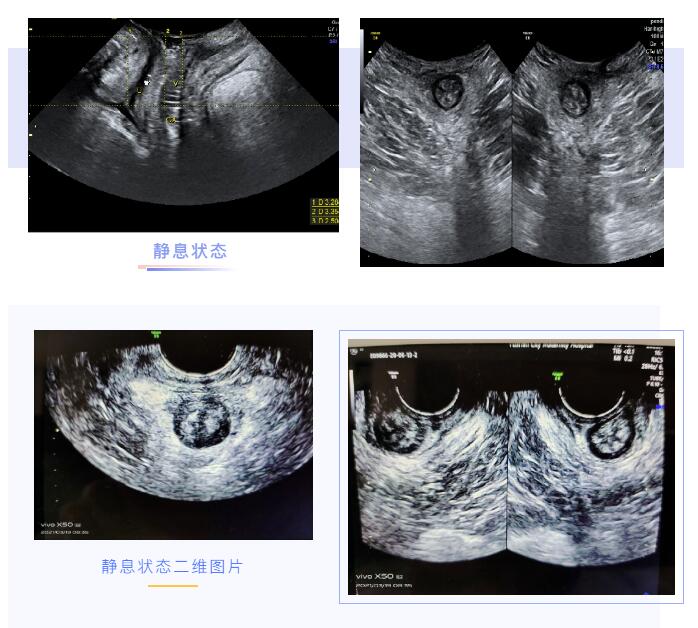

盆底超声就是应用超声探头经会阴来观察比较女性静息,缩肛,Valsalva状态盆腔器官的变化,评估盆腔器官下移程度及盆腔肌肉组织损伤程度。

可以实时动态观察不同状态下盆底结构和功能的变化

可以直接观察盆腔脏器的结构和位置改变

可以获得盆底完整的声像图